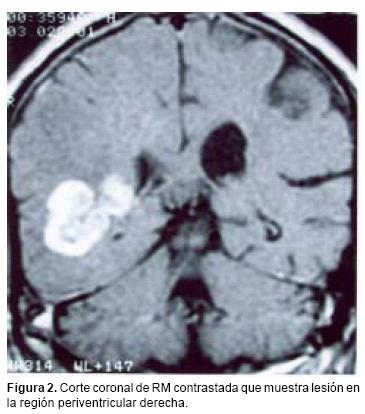

En los estudios de imagen, el LPSNC se manifiesta por lesiones únicas o múltiples, generalmente en la región peri–ventricular y éstas muestran diferentes patrones de reforzamiento con el medio de contraste, dado que tiende a ser anular en casos de pacientes con inmunodeficiencia, mientras que es homogéneo en los IC. Sin embargo, aun cuando los estudios de imagen sean altamente sugestivos del diagnóstico, es necesaria la confirmación histológica. Debido al tamaño y la localización de la mayoría de las lesiones en la profundidad del parénquima cerebral, es innegable que el mejor método para obtener el diagnóstico es la biopsia por estereotaxia.12,13 Sin embargo, este procedimiento presenta algunos problemas: en primer lugar, en ocasiones no es posible obtener una cantidad suficiente de tejido para efectuar el diagnóstico correcto; en segundo lugar, la mayoría de los pacientes con estas lesiones ya han sido tratados con esteroides antes de la cirugía, medicamentos que han demostrado tener un efecto citotóxico en los linfomas cerebrales, condicionando una reducción en el tamaño o hasta desaparición del tumor. Este hecho dificulta no sólo el diagnóstico histológico sino la toma de biopsia en sí misma.

La distribución por sexo de los 22 pacientes, fue equitativa (Cuadro I) con un promedio de edad de 65 años (límites entre 43 y 92 años). Cinco pacientes refirieron antecedentes neoplásicos heredofamiliares en rama directa: dos carcinomas cervicouterinos, dos adenocarcinomas de pulmón y un carcinoma de células gigantes. En un solo paciente se encontró antecedentes personales de neoplasia, por melanoma diagnosticado 10 años antes. El tiempo promedio entre la aparición del primer síntoma y la hospitalización fue de 80 días (límites entre 7 y 730), el cual fue con mayor frecuencia cefalea asociada a déficit neurológico focal. Un paciente presentó síntomas inespecíficos, tales como febrícula y alteraciones gastrointestinales antes del inicio del cuadro clínico, sin asociación al padecimiento neurológico. El promedio de calidad de vida de acuerdo a la escala de Karnofsky26 fue de 62.7 años. Los estudios radiológicos mostraron en cuatro pacientes lesiones múltiples, mientras que en el resto fueron lesiones únicas. La localización de cada lesión fue como sigue: 21 en los hemisferios cerebrales (ocho parietales, seis frontales, cuatro temporales y tres occipitales), seis en los núcleos basales, cuatro en el cuerpo calloso y uno en el tallo cerebral. En la tomografía computada las lesiones se apreciaron isodensas con discreta tendencia a la hiperdensidad y con un reforzamiento regular y marcado a la administración del medio de contraste (Figura 1). En la resonancia magnética, las lesiones aparecieron como iso o discretamente hipointensas en T1, con evidente y homogéneo reforzamiento con la aplicación del medio de contraste (Figura 2); en la fase T2 la mayoría de las lesiones eran hiperintensas, acompañándose de un marcado edema circundante. El tamaño promedio de los tumores fue de 22 mm (límites entre 3 y 57 mm), localizándose la mayoría de ellas en la región periventricular o subcortical, adyacentes a la circulación del líquido cefalorraquídeo; en el cuerpo calloso se ubicaban principalmente en el esplenio (Figura 3).